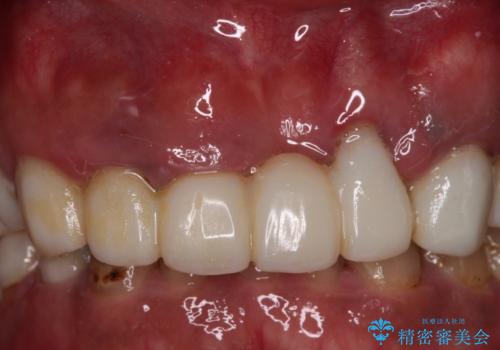

欠損と虫歯だらけの口の中 真っ白なセラミック治療

- 奥歯の欠損や、ボロボロになった歯を気にして来院された患者様です。

インプラントにより奥歯の咬み合わせが安定し、上顎前歯の歯肉ラインを調整するための骨外科処置により深く咬みこんでいた前歯部も負担のかからない咬み合わせに改善することができました。